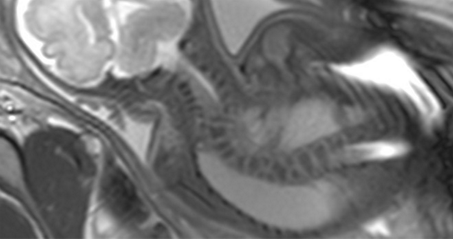

胎儿磁共振检查不存在电离辐射,它的视野大、软组织分辨率高,可以通过任意的切面扫描来显示胎儿的全貌。并且不受母体过度肥胖、羊水过少、多胎、母体子宫肌瘤、胎儿骨骼遮挡、孕晚期胎头入盆等情况的限制,尤其对胎儿颅脑发育评估有无可替代的优势。

1.诊断价值最大的是胎儿中枢神经系统异常:临床常见检查原因如后颅窝池宽,需要MRI来确认是否为Dandy-Walker畸形、Joubert综合征、蛛网膜囊肿、Blake囊肿等;后颅窝显示不清,需要除外ChiariⅡ畸形。其次为侧脑室宽,需要MRI确认是否合并胼胝体发育不全、结节性硬化、脑回发育畸形、脑出血、脑肿瘤、脑积水、积水性无脑、前脑无裂畸形、脑脊膜膨出等。确认超声软指标异常是否合并严重畸形对于妊娠结局至关重要。